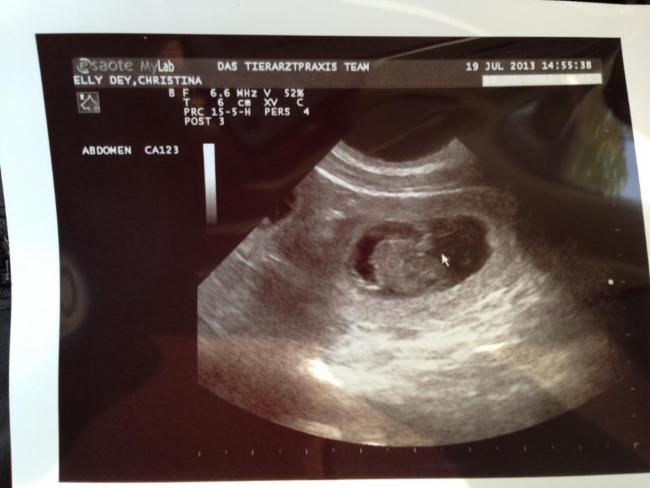

4. Woche | Am 22. Tag sind die Embryonen sichtbar. Der Herzschlag kann zur Diagnose der Trächtigkeit herangezogen werden. Anstrengende Aktivitäten sind jetzt zu vermeiden.Die Proteinzufuhr im Futter kann erhöht werden. Hierfür eignet sich sehr gut die Gabe von Welpenfutter. Zu diesem Zeitpunkt kann mit einer Ultraschalluntersuchung der Zustand der Trächtigkeit festgestellt werden. Besprechen Sie mögliche Risiken einer solchen Untersuchung mit dem Tierarzt. |

Do, 18.07.2013 bis Mo, 22.07.2013 | Dies ist der beste Zeitpunkt, um die Trächtigkeit anhand des Herzschlags zu diagnostizieren. Die Embroynen sind etwas walnussgroß und sind gleichmäßig im Uterus verteilt. |